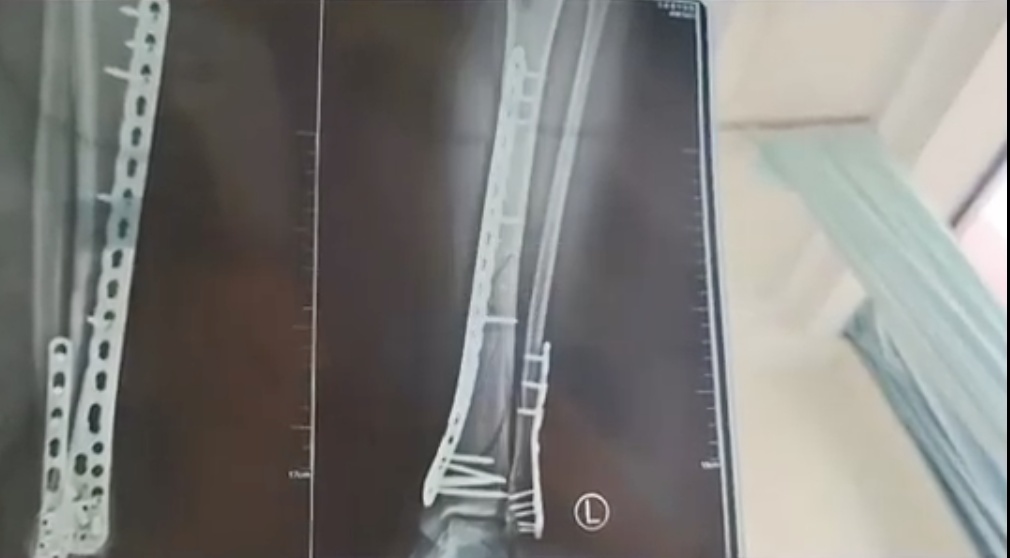

女子穿7cm厚洞洞鞋崴脚

致左腿粉碎性骨折

近日,甘肃兰州的武女士称母亲节当天,自己穿7cm厚洞洞鞋下楼,不慎崴脚摔倒,致使自己左腿粉碎性骨折。

该女子称,目前已做完手术在家休养,不过下地得拄拐才行,且下地有时间限制,不能久站,而骨折完全康复可能需要3个月,她提醒大家穿增高鞋要注意。